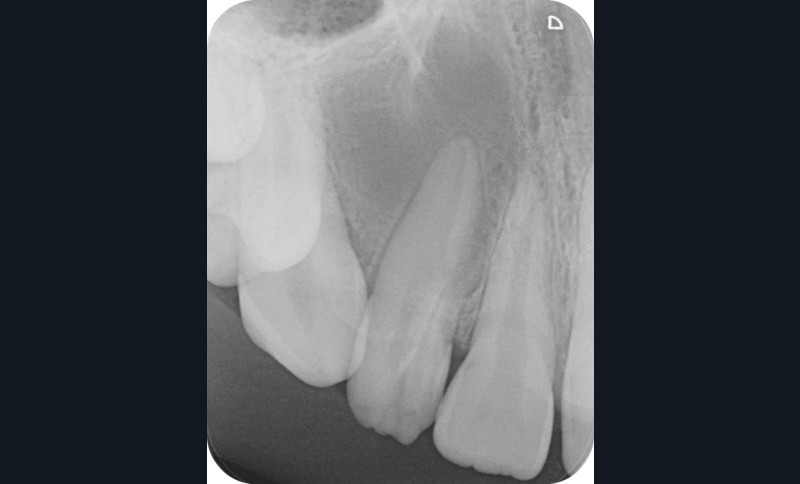

La patiente, âgée de 12 ans, s’est présentée à ma consultation avec une demande du chirurgien de réaliser le traitement endodontique de la 12 avant le curetage sous anesthésie générale. La radiographie périapicale préopératoire a mis en évidence une anatomie complexe. Les tests préopératoires ont montré un sondage parodontal sain, une percussion positive et un test au froid positif. La patiente présentait également une fistule vestibulaire active. Le Cone Beam a mis en évidence la présence d’une dens in dente et d’une lésion imposante ainsi qu’une palatoversion importante de la racine de la 12. La lésion est-elle responsable de ce mouvement dentaire ? (fig. 1, 2 et 3).